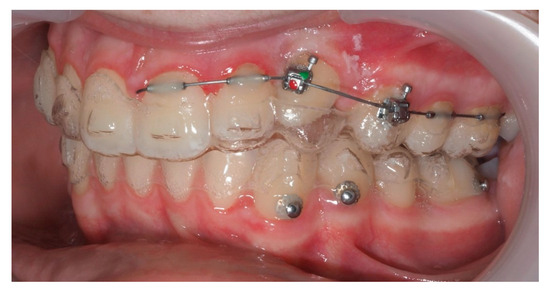

Approximately 7 months later, a palatal mini-implant was placed between teeth 24 and 25, serving as stable anchorage for distal traction using an elastic chain, which was replaced monthly (Figure 15). This movement positioned the canine away from the lateral incisor root. Aligners were customized and adjusted throughout treatment.

Figure 15.

Adjusted aligners, palatal mini-implant, and elastic chain used for distalizing the canine; 7 months after the surgery.

Following initial distalization, a sectional fixed appliance was bonded from tooth 11 to 26. On tooth 24, a bracket with a metallic ligature was used to support Class II elastics. Mini-tubes were bonded on teeth 22, 25, and 26, and the aligners were trimmed accordingly (Figure 16). A ligature wire connected the palatal button on the canine to a 0.014” nitinol archwire (Figure 17).

Figure 16.

Sectional fixed appliance from teeth 11 to 26, with support for Class II elastics to improve sagittal relationship; 14 months after the surgery.